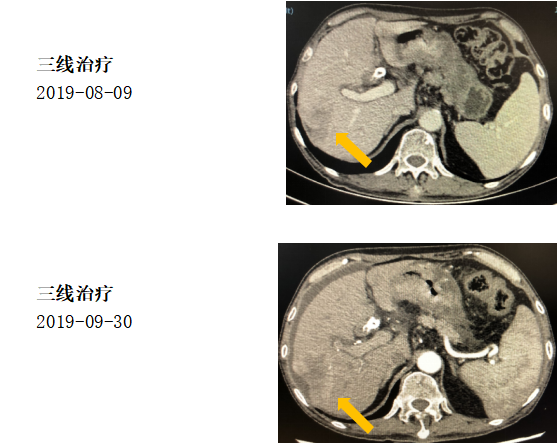

治疗经过:三线治疗

具体治疗方案:

纳武利尤单抗140mg;

赫赛汀6mg/kg,每3周重复。

2019-08-09至2019-09-30,肝内病灶较前增大,2周期纳武利尤单抗+赫赛汀治疗后肿瘤PD。